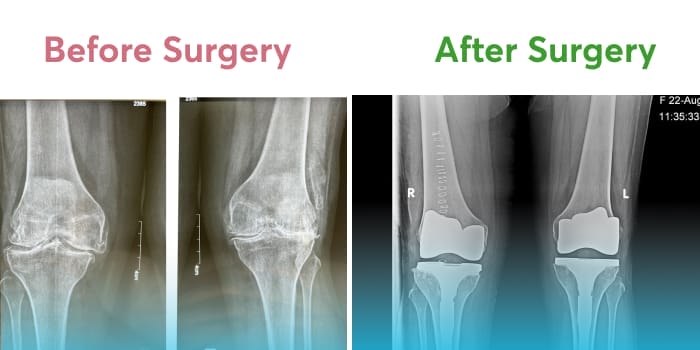

The knee joint is the biggest in the human body, connecting the thigh-bone or femur to the Tibia or shin-bone in the lower leg. The knee joint is a hinge-type synovial joint and one of the most complex joints in the body. It is a network of ligaments and muscles that keeps the body sturdy while standing or moving around. The most important components of the knee joint are the Meniscus and other ligaments like PCL, ACL, MCL, and LCL.